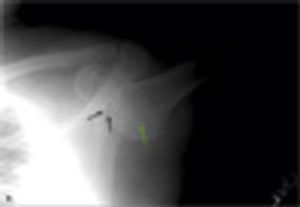

While jogging in a park, a 45-year-old man tripped and fell on his outstretched hand. As he fell, he tried to catch himself on a nearby park bench but was unsuccessful. He felt that his shoulder was out of place, and he was unable to adduct his arm from its erect position. A witness called for an ambulance, and the man was taken to the emergency department.